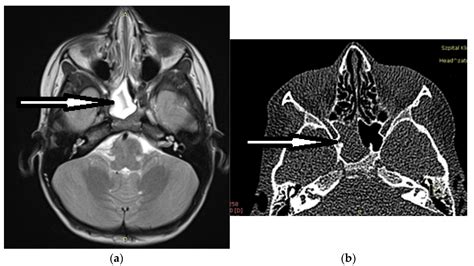

• Imaging Tests: CT scans or MRI scans to visualize the sphenoid sinuses and surrounding structures. These tests can help identify any abnormalities, blockages, or infections.